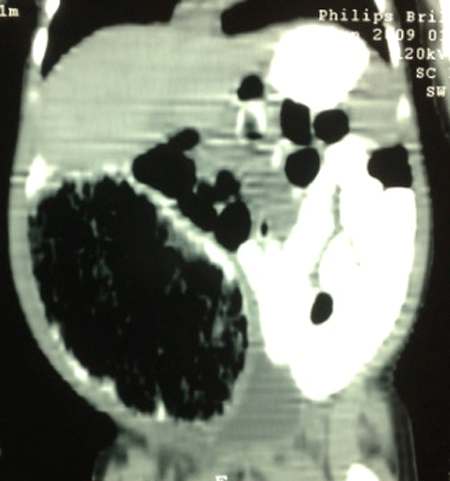

Case 2:A 2-month-old male baby, previously operated on 2nd day of life for omphalocele minor, presented with abdominal distention associated with regurgitation of feed and irritability. On examination, there was a palpable mass which was soft, smooth, and slightly mobile. The erect abdominal radiograph showed a soft tissue shadow in the right iliac fossa pushing the bowel to the other side. CT scan of the abdomen showed huge cystic mass in the abdomen (Fig. 3). On exploration there was a cystic duplication of the terminal ileum which was excised along with resection of the bowel related to the cyst with end to end anastomosis. Patient is doing fine on follow-up.

Figure 3: CT scan of the abdomen showing huge cyst in the right abdomen |